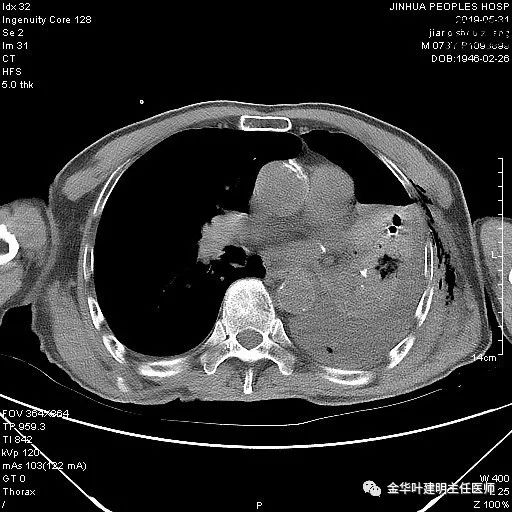

考虑左侧大量胸腔积液,遂进一步胸部CT检查:

以上是肺窗表现,下面为纵隔窗影像: